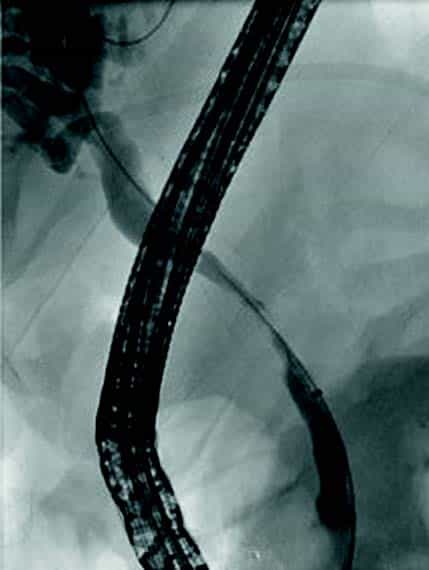

Små konkrementer i pankreas hovedgang (< 5 mm) kan ofte fjernes endoskopisk ved at strikturer dilateres og konkrementet hentes ut med konvensjonelle metoder (Fig 4). Større konkrementer er mer krevende og kan behandles med ESWL eller pankreatikoskopi og fragmentering av konkrement(ene) med sjokkbølgelitotripsi eller laser. Selv om man tilsynelatende klarer å fjerne alle konkrementer fra hovedgangen er tilbakefallsfrekvensen høy og pasientene risikerer langvarig stentbehandling (vanligvis en eller flere plaststenter) og gjentatte endoskopiske prosedyrer.

Obstruksjon av gallegang

Inflammasjon og fibrose i caput av pankreas kan skade gallegang og føre til benigne strikturer og kolestase. Slike strikturer kan være krevende å behandle. Det er viktig med god bildediagnostikk i forkant av terapi for å utelukke malign striktur, noe som kan være vanskelig på grunn av de inflammatoriske/fibrotiske forandringene sekundært til kronisk pankreatitt. Det er svært viktig at man ikke intervenerer endoskopisk dersom usikkerhet om malign etiologi men henviser til senter med HPB kirurg og MDT vurdering. Standard behandling av benigne strikturer har vært ERCP med gjentatte dilatasjoner og innleggelse av multiple plaststenter i gallegang over en periode på ett år (Fig 5). De senere år har bruk av selvekspanderende metallstent i 6-12 mnd. blitt mer vanlig dersom forholdene teknisk ligger til rette for dette. Det er imidlertid risiko for residiv av striktur på grunn av progresjon av grunntilstanden så gjentatt endoskopisk behandling kan bli nødvendig.

Fig 5: Pasient med gallegangsstriktur sekundært til kronisk pankreatitt som behandles med endoskopisk ballong dilatasjon og stenting av gallegang.